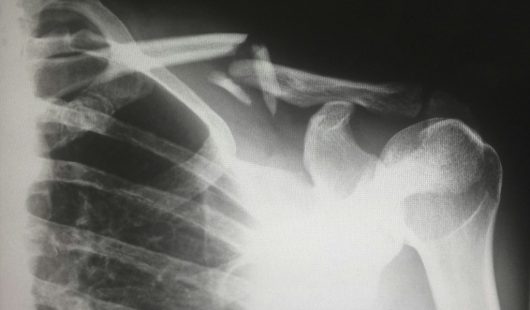

Collarbone Fractures

• Often caused by impact injuries, falls, or road traffic accidents.